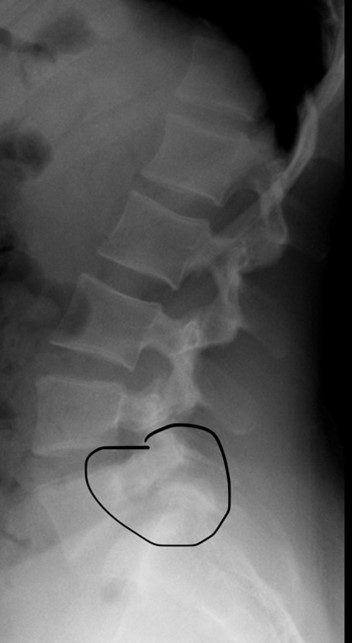

Injuries to these posterior elements can range from soft tissue overload (such as muscle strains) to bone stress injuries including stress fractures (called spondylolysis in medical terms).Â

Picture of stress fracture in pars interarticularis of L5 (circled). In this case, the body of L5 has slipped forward due to pars stress fractures on both sides of L5. This condition is called spondylolysis.